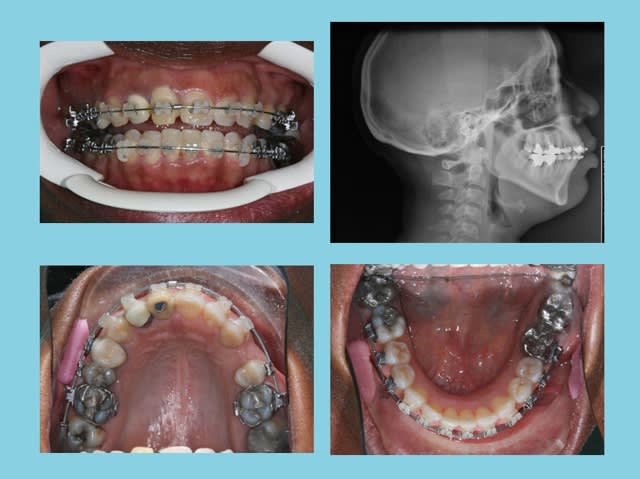

suite

au lieu d'extraire une Inc. Inf.

Augmentation de longueur d’arcade = 15 mm.

Rien qu'à la PANO., on peut voir que les rapports 22/33 sont modifiés

dans l'état actuel de nos techniques, oui, ça a été facile, 2 ans, bien que maintenant, je sais que j'aurais pu gagner 6 mois

encore qq. mois avant la contention!